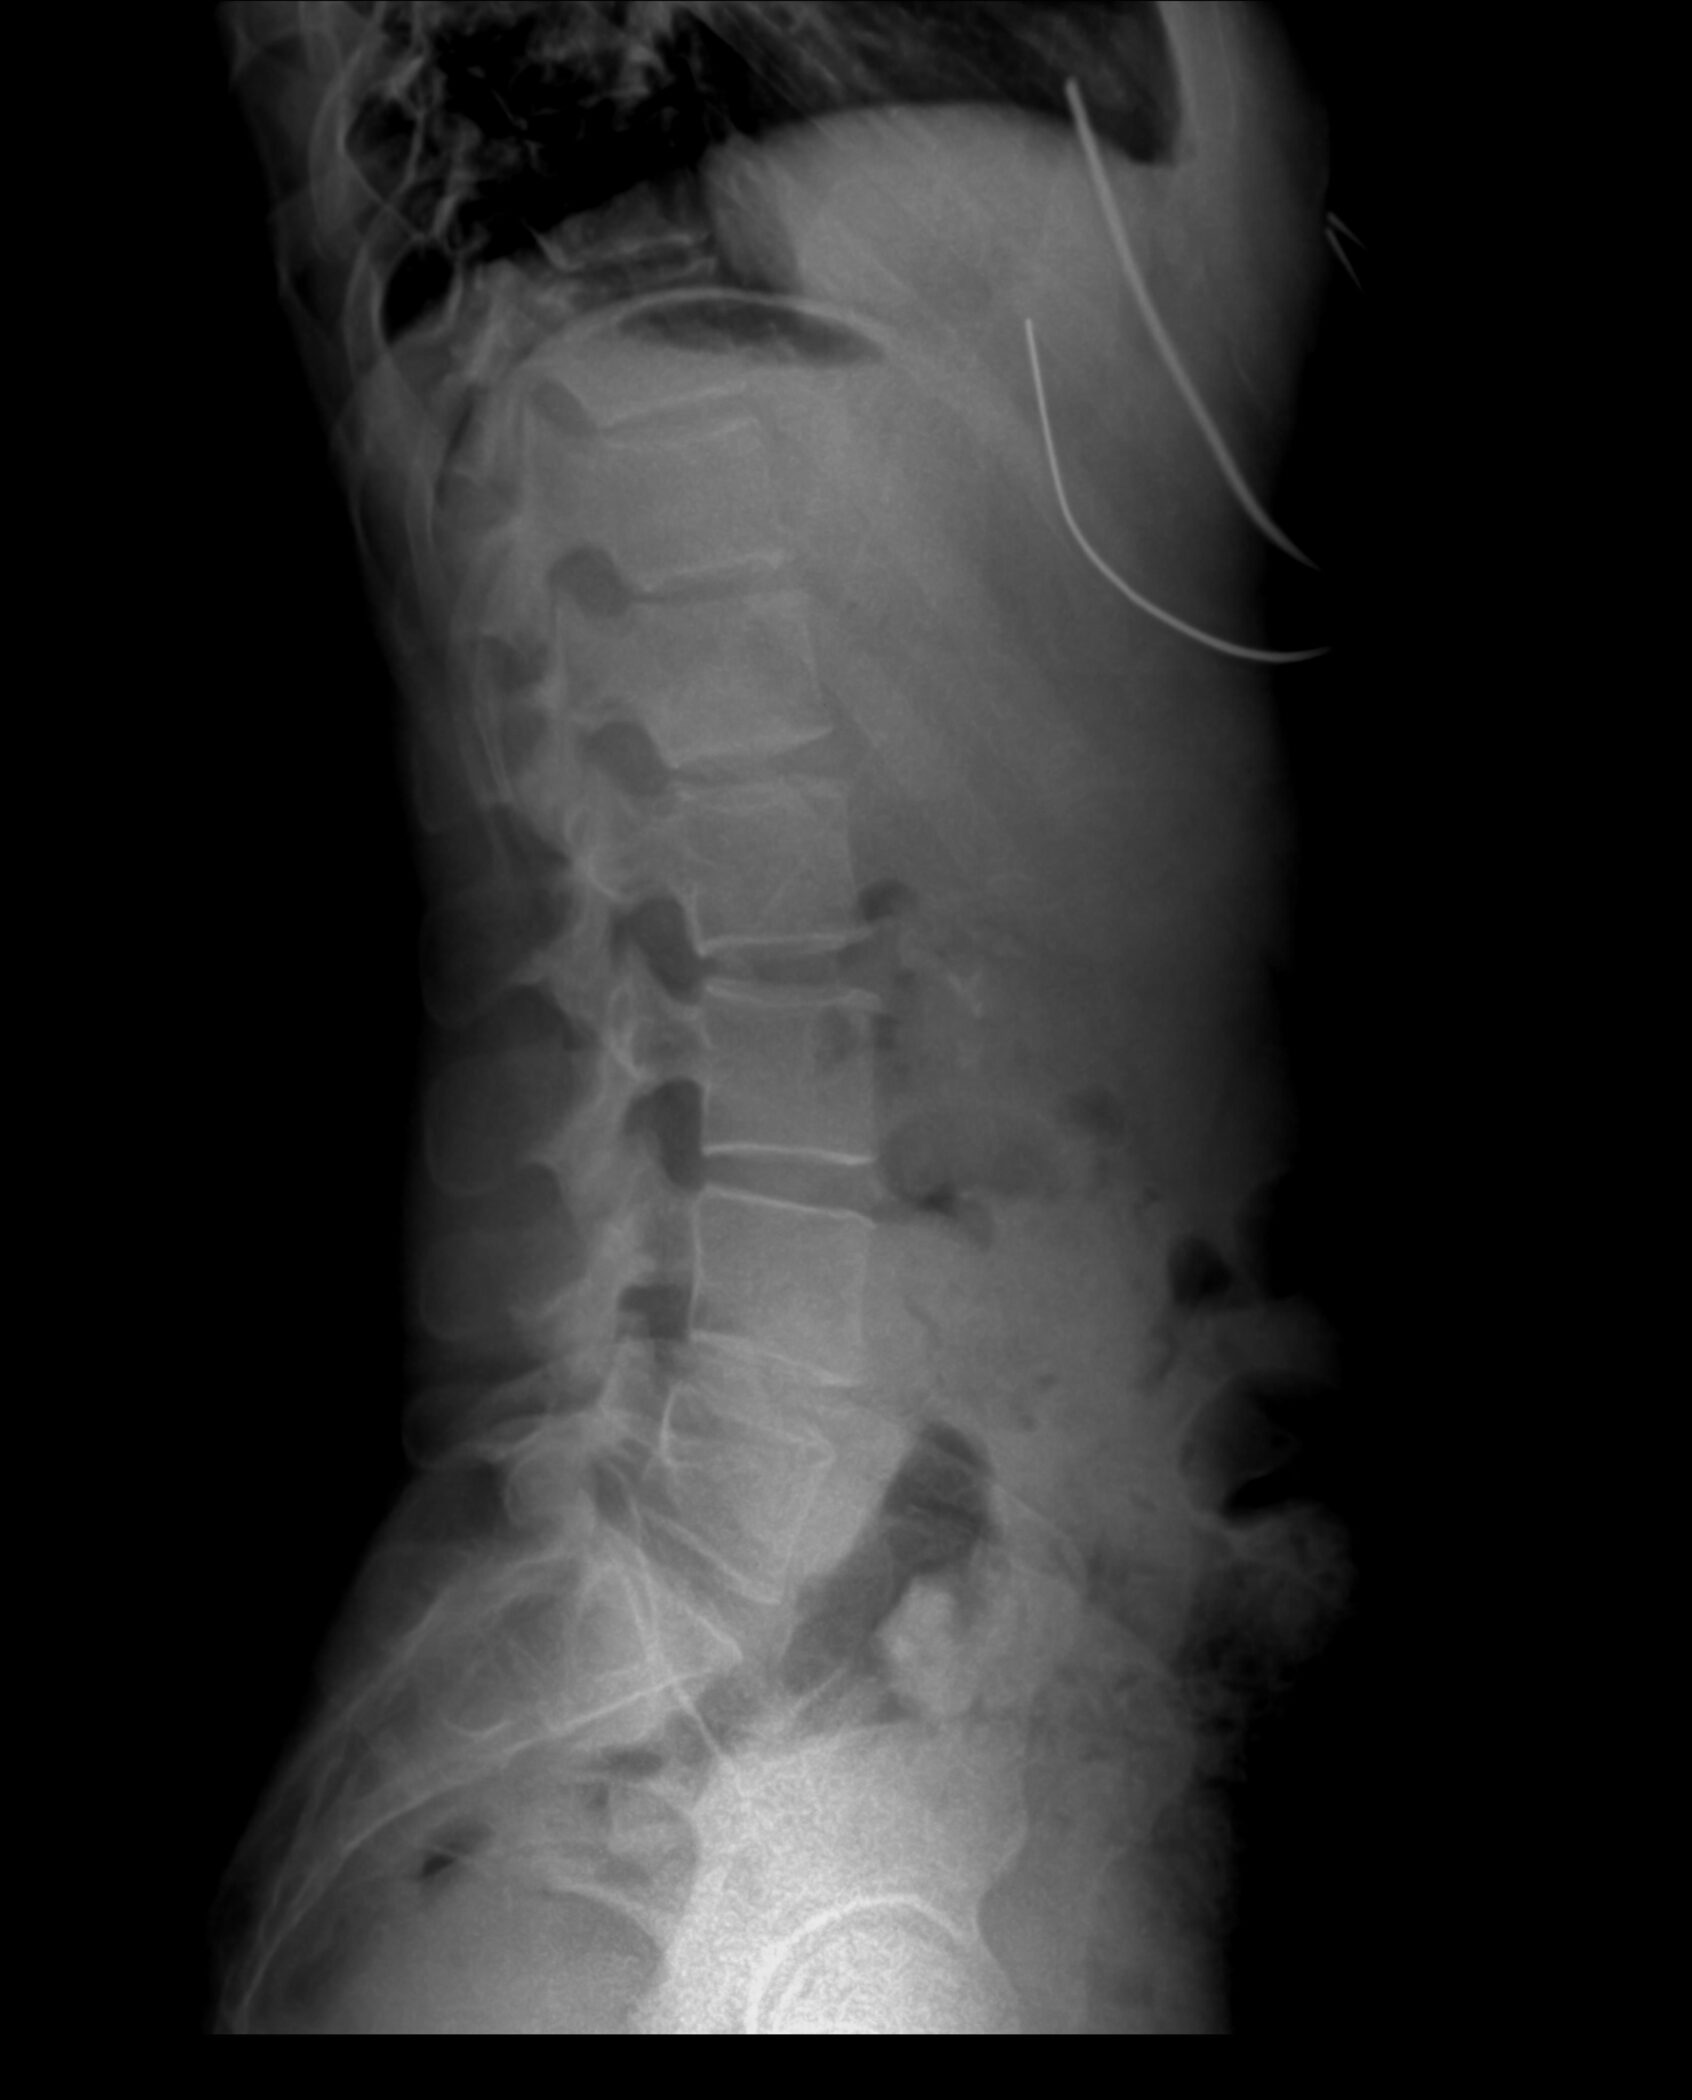

The spinal cord transmits signals between the brain and body. When damaged, movement or sensation can be impaired. Specifically, a spinal cord injury (SCI) from chiropractor malpractice may result from improper techniques. Moreover, these injuries range from incomplete to complete, affecting function below the injury site. Thus, understanding chiropractic risks is crucial.

- Negligent Cervical Manipulation: Spinal manipulation, particularly when performed on the upper spine, is frequently associated with mild to moderate adverse effects. It can also result in serious complications such as vertebral artery dissection followed by stroke (source). High-velocity neck adjustments can cause vertebral artery dissection or spinal cord compression, potentially leading to stroke, paralysis, or pinched nerves.

- Failure to Order Diagnostic Imaging: Not conducting X-rays or MRIs before adjustments may miss underlying conditions, increasing injury risk.

Medical evaluation involves diagnostic tests like MRIs. Stabilization, such as braces, may be needed. Medications can reduce swelling, while rehabilitation aids recovery. Furthermore, long-term care may be required for chronic conditions. Thus, a team of specialists ensures comprehensive treatment after chiropractor malpractice.